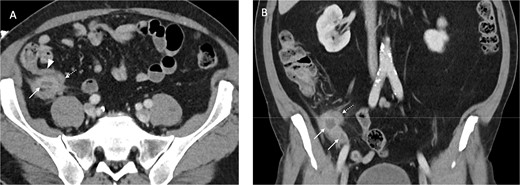

Contrast enhanced axial (A) and coronal (B) CT images in portal venous phase demonstrate periappendiceal abscesses (solid arrows) closely associated with thick-walled and inflamed tip of the appendix (dashed arrows). Note the normal appearing base of the appendix (arrowhead in A).